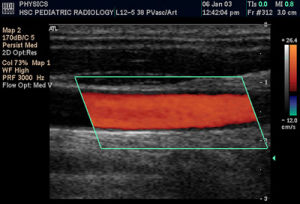

頸總動脈彩色超聲都卜勒聲像圖經顱彩色都卜勒檢查可以判定腦底動脈環、大腦前動脈大腦中動脈、大腦後動脈頸內動脈顱內段及椎基動脈等顱內大血管的血管深度血液方向、血流速度和搏動指數等,依此可判定哪根血管有病變。